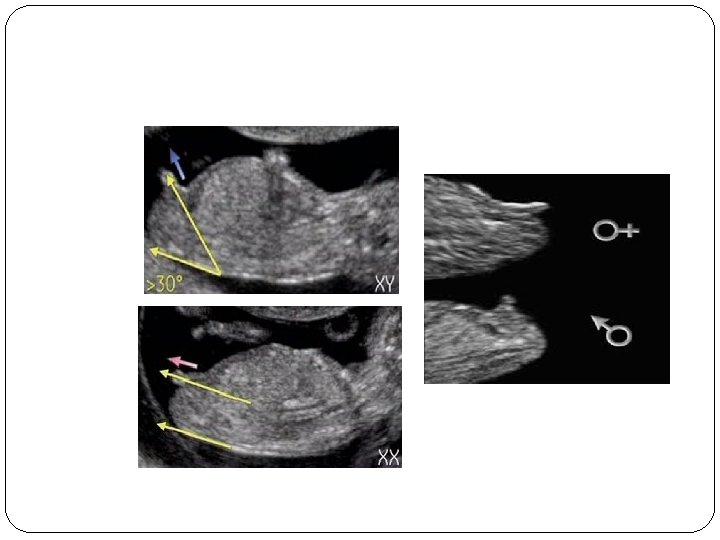

Gender Determination

Gender Determination • Deciding whether to carry out prenatal invasive testing in pregnancies at risk of sex-linked genetic abnormalities Just necessary in male fetuses • Angle between the genital tubercle & a horizontal line through the lumbosacral skin surface: ü ü Male if Female if > 30° Parallel or Convergent (< 20°)

Technique • GA: 12 - 13+6 wk • Mid-sagittal section of the fetus in the neutral position (Fetus may either be facing towards the transducer) • No extension of the limbs or spine CRL = 54 - 84 mm

Test Properties Male Female (Wrong assignment) 11 wks 56% 5% 12 wks 3% 0% 13 wks 0% 0% Gestational Age o Test accuracy: ü 11 wks. ü 12 wks. ü 13 wks. 70. 3% 98. 7% 100% o In the male fetuses, there is a significant increase in the angle of the genital tubercle from the horizontal with CRL increment o Final decision should be undertaken only after 12 weeks